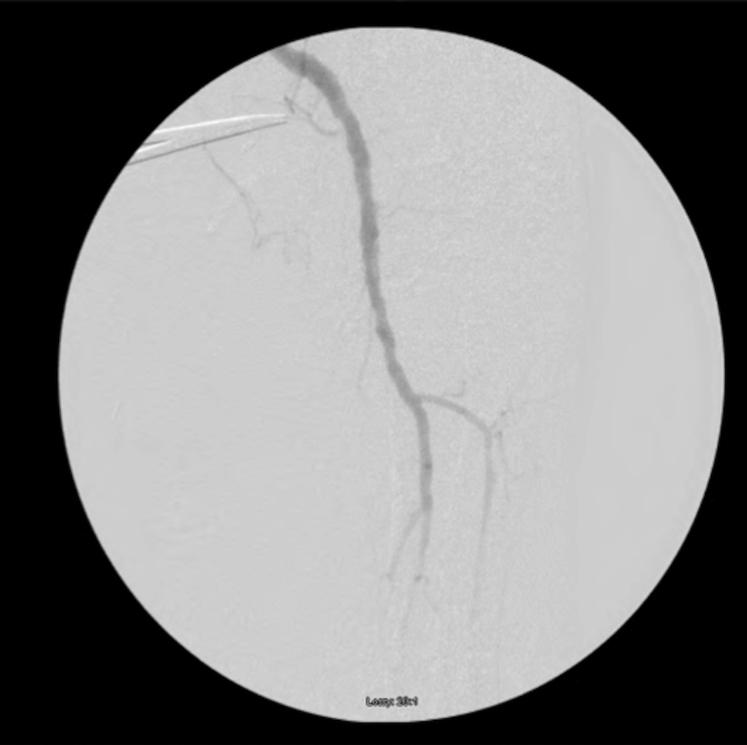

A 96-year-old male presented with left lower extremity pain, swelling, and vascular compromise. Computed tomographic angiography revealed an actively rupturing distal superficial femoral artery aneurysm. The patient underwent prompt aneurysm excision with graft interposition and had a successful postoperative outcome. Our case illustrates the critical role of imaging in establishing a definitive diagnosis and preventing mortality.

一名96岁男性出现左下肢疼痛、肿胀及血管受压症状。计算机断层血管造影显示股浅动脉远端动脉瘤正在破裂。患者迅速接受了动脉瘤切除并植入移植物,术后恢复良好。我们的病例说明了影像学在明确诊断和预防死亡方面的关键作用。